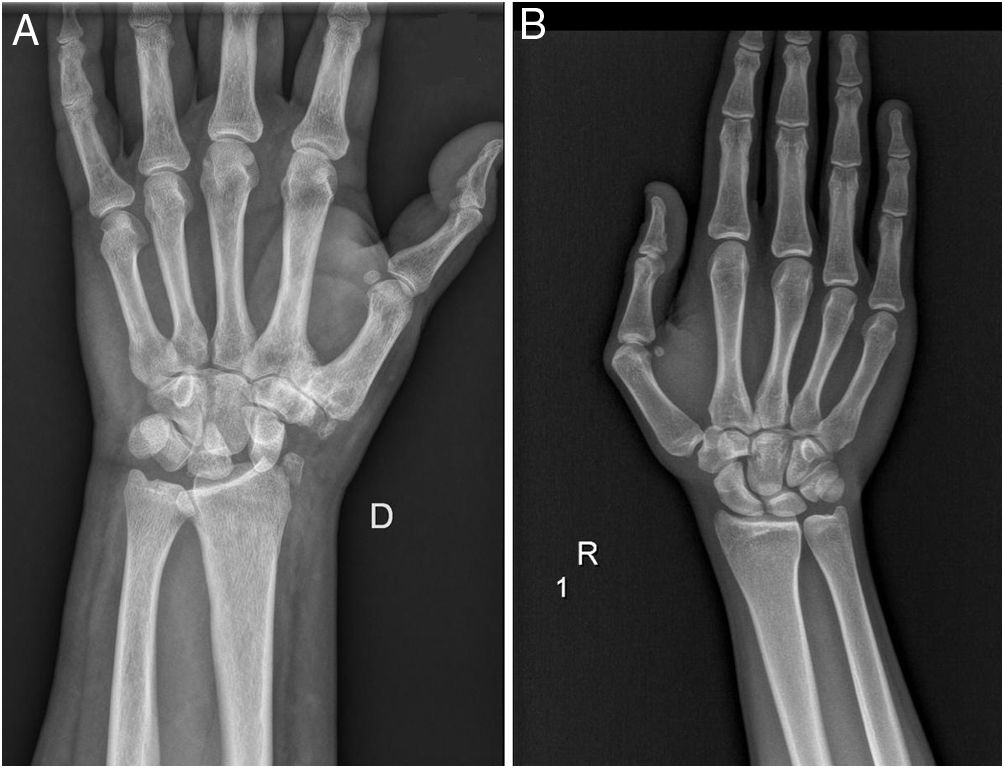

Las imágenes fueron enviadas a los observadores mediante correo electrónico en una presentación PowerPoint (Microsoft Office 2010; Microsoft, Redmond, Washington) en el que, tras una breve explicación de los arcos de Gilula que incluía una imagen demostrativa (fig. 1), se presentaban las 30 imágenes, patológicas y normales, mezcladas aleatoriamente (fig. 2). Los observadores sólo tenían que decir si la imagen mostrada era normal o patológica, o lo que es lo mismo, si las líneas de Gilula estaban conservadas o no, en un formulario creado para tal efecto, asignándoles los valores 0 o 1 respectivamente.

Proyección PA de muñeca con las tres líneas o arcos de Gilula dibujadas. El primer arco recorre la superficie articular proximal convexa de escafoides, semilunar y piramidal; el segundo arco recorre la superficie articular distal cóncava de los mismos huesos; el tercer arco recorre la superficie articular proximal convexa de los huesos grande y ganchoso.